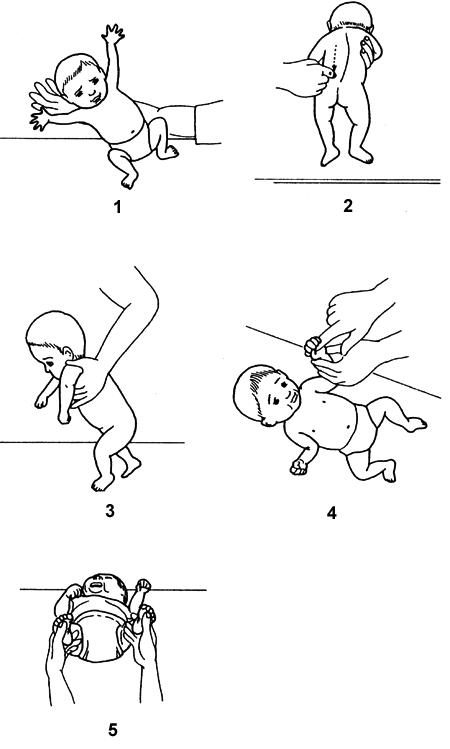

図は痙直型両麻痺を示す脳性麻痺児(GMFCSレベルⅢ)の長座位姿勢である。後方に倒れるのを防ぐため上体を起こそうと全身の筋緊張を強め努力している。その際に上肢に起こる連合反応として適切なのはどれか。

1

肩甲骨の挙上

2

肩関節の外転

3

肘関節の伸展

4

前腕の回外

5

手関節の背屈